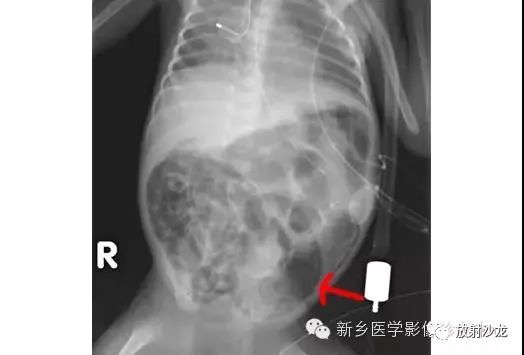

上图是一个孩子所做的腹部平片。有什么不好的发现(通过箭头的引导)?该平片显示坏死性小肠结肠炎患儿出现肠壁积气。肠壁积气是肠管缺血后的肠壁内的空气集聚。肠壁(箭头)出现线性的或曲线的透亮。在少数情况下,肠壁积气可以是慢性阻塞性肺病、腹部疾病、结缔组织疾病、使用类固醇类药物或化疗所致。

虽然X线平片足以诊断三分之二的肠壁积气病例,但CT可以更清楚地证明这种过程。CT上肠壁积气清晰可见(箭头)。